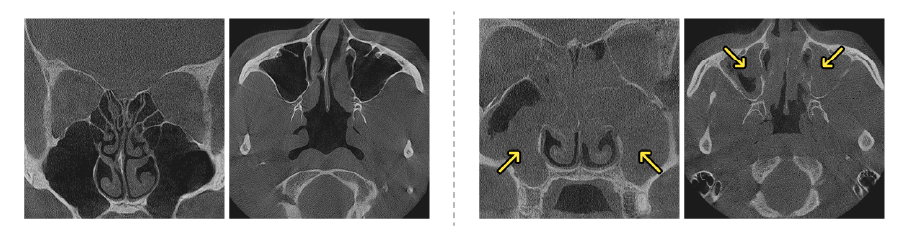

부비동 내시경 수술 설명 정상 부비동 CT 만성 부비동염 CT

부비동 내시경 수술 설명 2 부비동 내시경 수술 전 부비동 내시경 수술 3개월 후